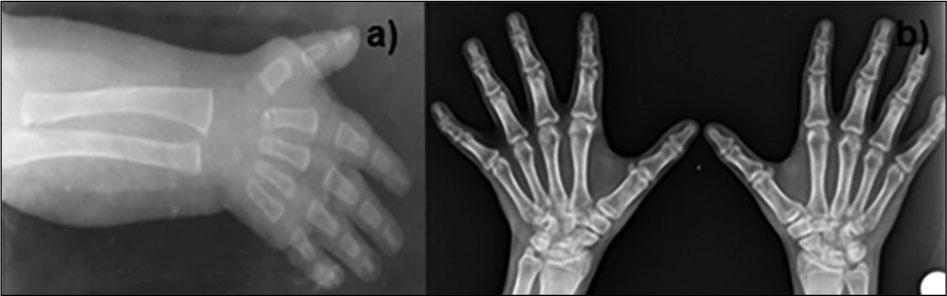

Skeletal problems present in this case were scoliosis, small hands and feet, brachydactyly, clinodactyly, tapering fingers. There is slight cutaneous syndactyly between the second and third toe (Figure 2). The dermatoglyphic pattern was unusual because the thenar crease was absent and there was a short hypoplastic mid-palmar crease. The fifth finger had a single flexion crease on its volar surface (Figure 3b). X-ray examination of hands at 11 months (Figure 4a) and 16 years (Figure 4b) revealed the relative shortness of tubular bones, especially of distal and middle phalanges.

X-ray examination of hands at 11 months (a) and 16 years (b)